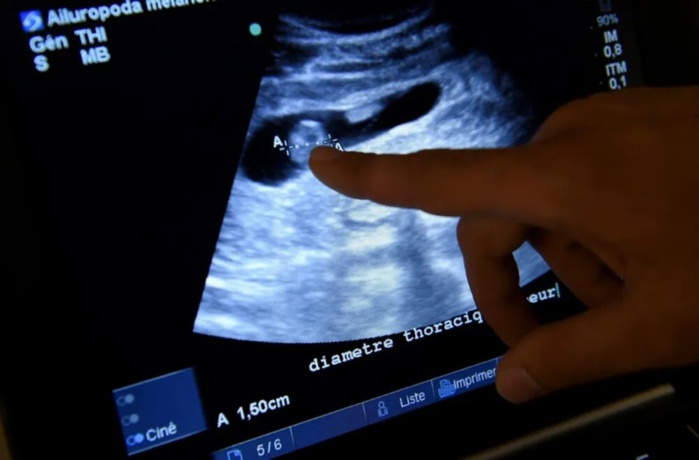

L'opération, pratiquée à l'hôpital pour enfants de Boston aux Etats-Unis et décrite comme "unique en son genre", visait à réparer un vaisseau sanguin malformé dans le cerveau du fœtus. La procédure a été effectuée au cours de la 34e semaine de grossesse. Les médecins ont indiqué que la même chirurgie, pratiquée après la naissance, n'aurait pas pu empêcher l'apparition de l'insuffisance cardiaque.

Né en mars, le bébé était en bonne santé et n'a eu besoin d'aucun médicament ni traitement depuis sa sortie de l'hôpital, selon l'article. Cette procédure, qui n'induit aucun effet négatif sur le cerveau, pourrait ainsi constituer un nouveau traitement pour la malformation de la veine de Galen (VOGM), qui est décrite par le Boston Children's Hospital comme un "type d'anomalie rare des vaisseaux sanguins à l'intérieur du cerveau" où les "artères déformées du cerveau se connectent directement aux veines".